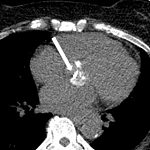

We are presenting the case of a 75-year-old female who tested positive for COVID-19 in the 2nd week of March with a high-resolution computed tomography (HRCT) score of 4/25 on the very next day for which she visited a hospital in sevagram where she was admitted for 7 days after which she was discharged and kept into home isolation under constant monitoring. After 2 months, on the 6th of May 2021 she was brought to the hospital in Sawangi, with complaints of pain over the right side of the face which was sudden in onset, continuous, dull aching, radiating to forehead on the right side with the history of associated swelling over the right side of the face which was initially small in size and gradually increased to present size of 3 x 2 cm approx, with history of difficulty in mastication, deglutition and speech were altered, nasal stiffness over the right side since 15 days. She is a known case of hypothyroidism for 20 years, diabetes mellitus and hypertension for 10 years with chronic kidney disease. On extraoral examination patient's face was asymmetrical due to fungal infection and diffused swelling over the right side of the face and opthalmoplegia, blurring of vision, ptosis, chemosis and restricted eye movements. Intraoral examination reveals mouth opening of 25mm with diffuse gingival swelling seen in the upper right maxillary alveolar region extending anteroposteriorly from 11 to 26 regions. Magnetic resonance imaging brain and orbit reveals invasive fungal sinusitis with the cutaneous collection and intracranial extension of mucormycosis.

Figure 1: (A,B,C) rhino orbital mucormycosis